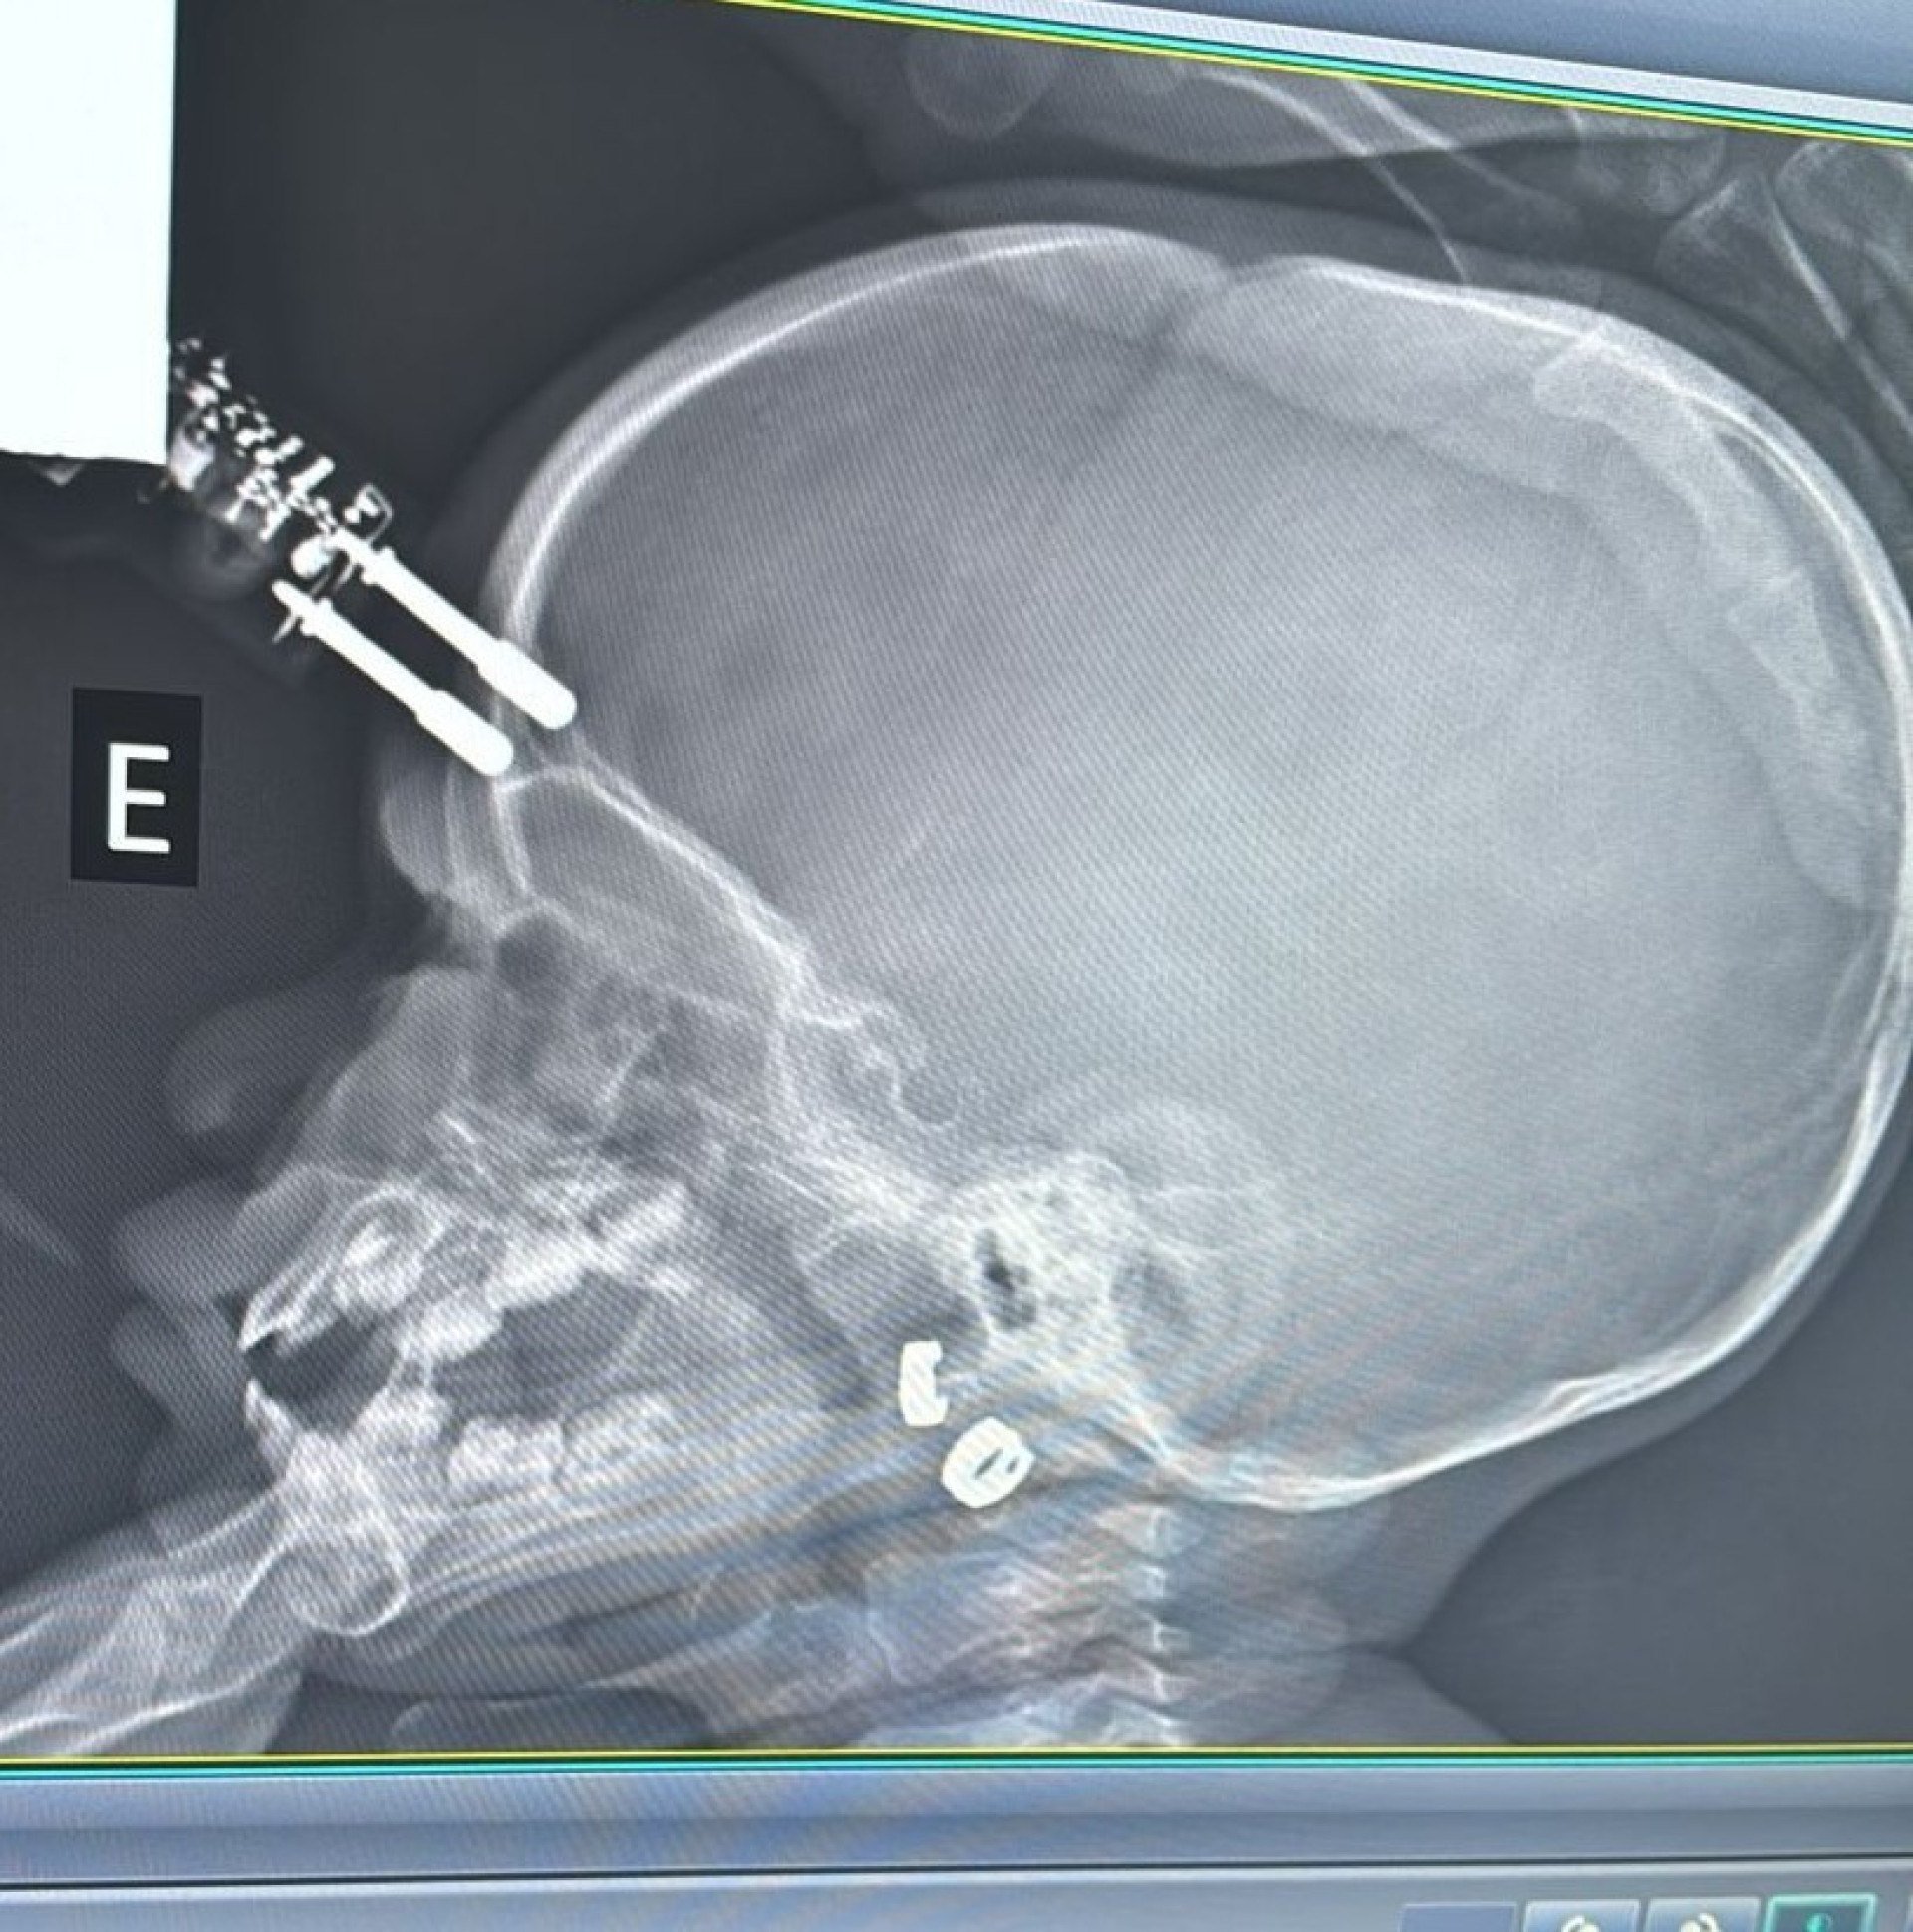

A criança foi levada inicialmente para a UPA de Divinópolis e, diante da gravidade, transferida pelo Samu para a sala vermelha do Hospital São João de Deus. Exames de imagem confirmaram que o pino havia transfixado o osso do crânio e atingido o cérebro. “O osso do crânio nessa idade é muito fino, tem apenas alguns milímetros. Pela tomografia, vimos que o objeto atravessou a calota craniana e lesionou a ponta do lobo frontal”, detalhou Bruno Castro.

Apesar da gravidade do ferimento, a criança estava consciente e foi levada imediatamente ao centro cirúrgico. O procedimento ocorreu sem intercorrências. “Foi uma cirurgia rápida e tranquila. Retiramos o corpo estranho, estancamos um pequeno sangramento e fizemos a correção da lesão. Ela acordou bem da anestesia e foi encaminhada ao CTI pediátrico”, afirmou o neurocirurgião.

A criança permaneceu 36 horas em observação intensiva e, após nova tomografia sem sinais de sangramento intracraniano, seguiu para a enfermaria. Por protocolo, recebeu antibiótico venoso durante cinco dias para prevenir infecções.